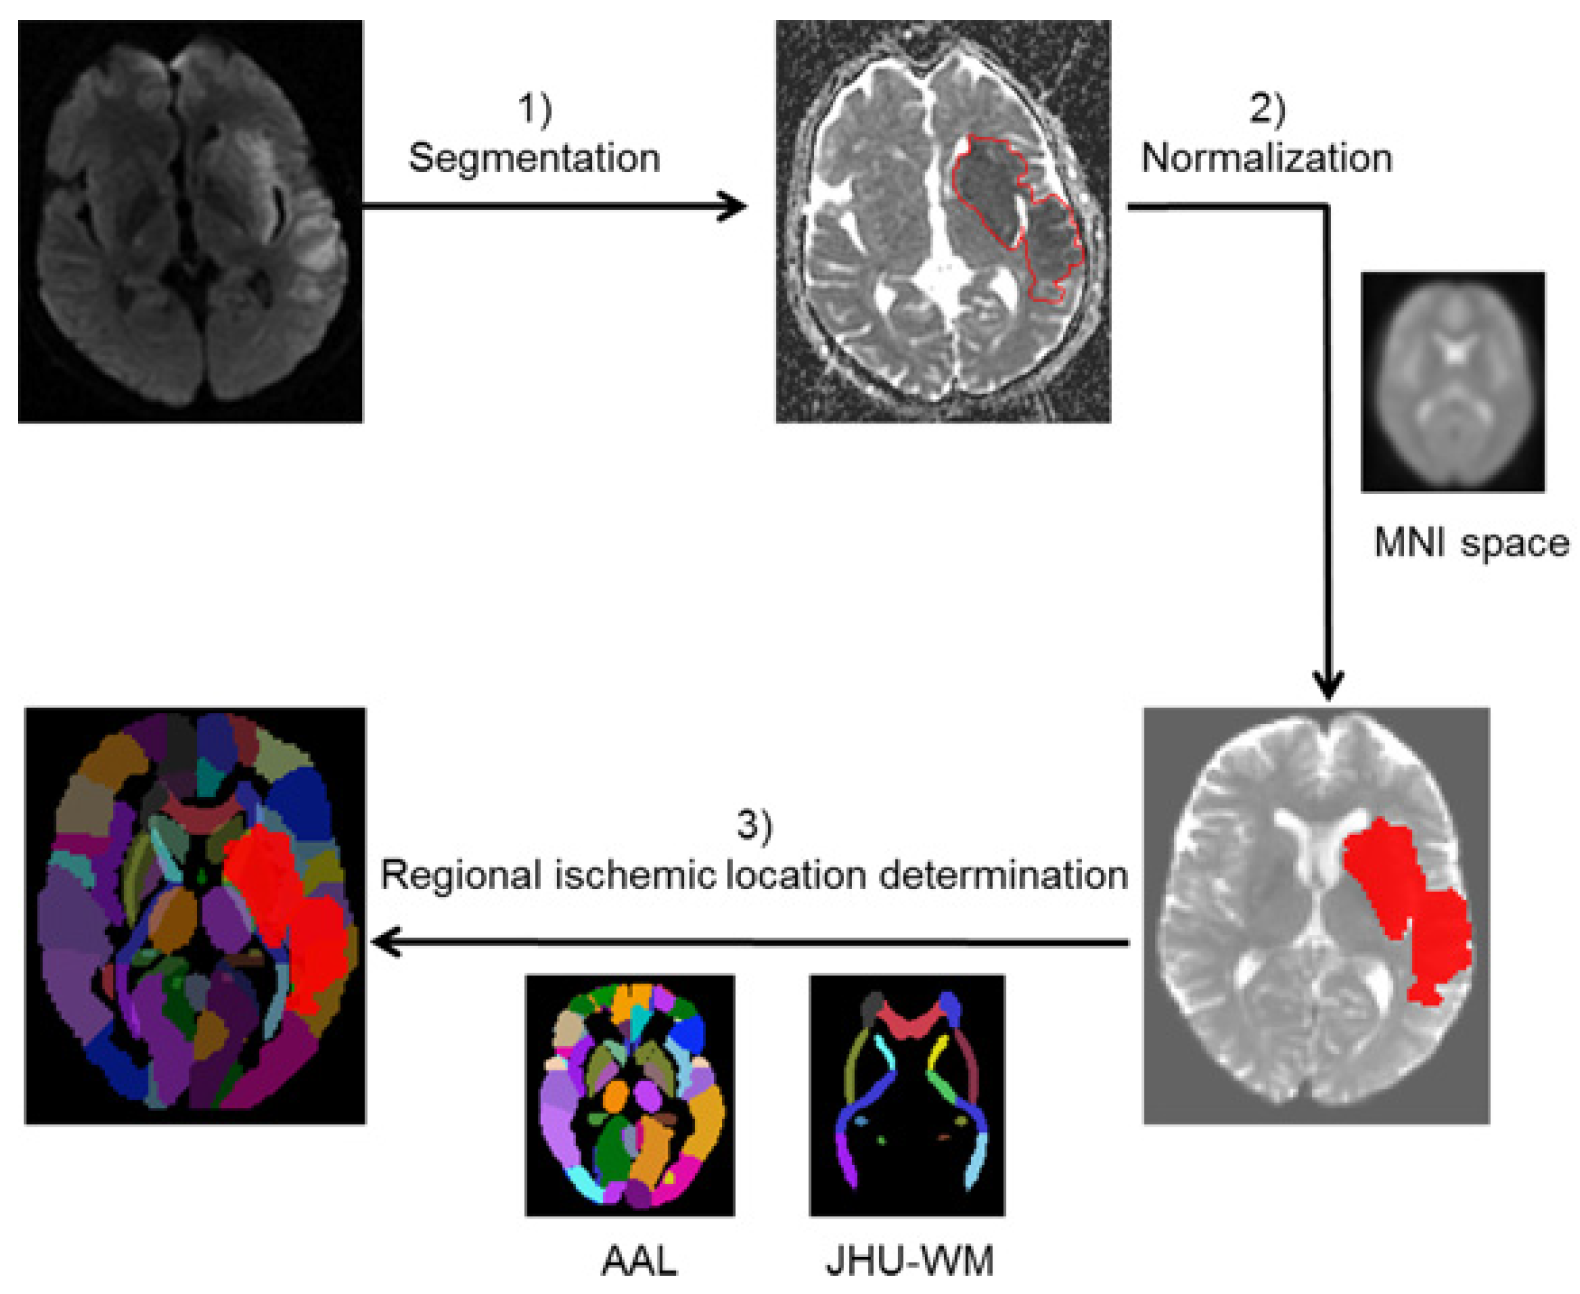

2.2. Image Acquisition, Segmentation, and Normalization

2.3. Regional Ischemic Location Determination